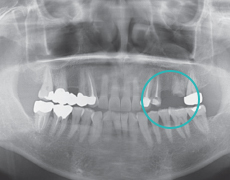

Präoperative UntersuchungDer Zustand des Bereichs im Mundraum wird geprüft und der Behandlungsplan wird festgelegt.

Schritt 4

Einbau der ProtheseEin künstlicher Zahn wird auf das Implantat eingebaut, um die Behandlung abzuschließen.